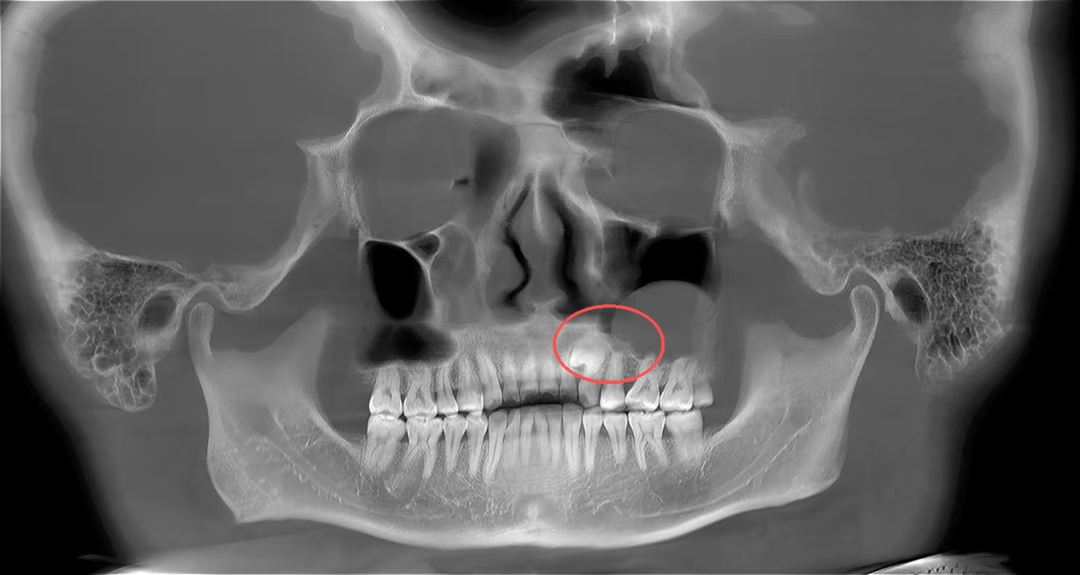

口腔颌面外科医生为其进行了详细的口腔检查并拍了放射片,结果显示:张先生的牙齿属于腭向埋伏阻生双尖牙,更值得注意的是,他的左侧上颌窦底还长有一个丘状软组织囊肿,且阻生牙的牙根与囊肿底部关系十分密切。

术后4个月,张先生复查时,伤口已经愈合得很好,没有任何不适,也没出现上颌窦炎等问题。拍片显示,上颌窦里的囊肿完全消失,拔牙的地方也长出了新骨头。